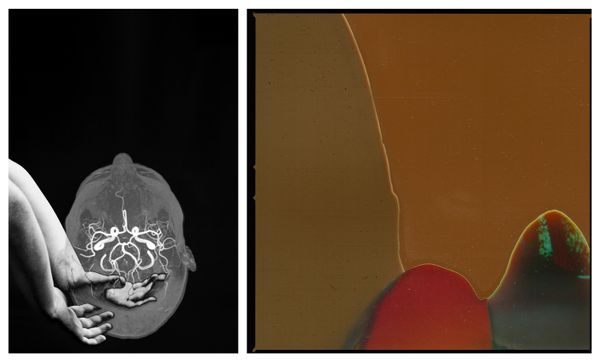

In pairing intricately constructed narratives with deconstructed, damaged film - the work in this series intends to convey the paradox of my neurodivergent mind, as I try to balance my desire to be seen with an overwhelming need to hide.

My internal timeline is non-linear, woven by fragmented memories of immense joy intertwined with medical traumas.

Utilising medical scans to illustrate pivotal moments in time where memories have formed, the work in this series pairs intricately constructed narratives with deconstructed, damaged film. Collectively, the images intend to convey the paradox of my neurodivergent mind as I try to balance my desire to be seen with an overwhelming need to hide.

JUST BREATHE, A SELF REFLECTION It's comforting to learn of my neurodivergence. Understanding it’s been there all along, informing all of my life’s experiences, explains so much to me about my medical history and the relationships I've formed with the people I love.

FALLINGIt’s as if all these fragmented pieces of me that were previously floating solo in their experiences have fallen into place, allowing me to see my whole picture.